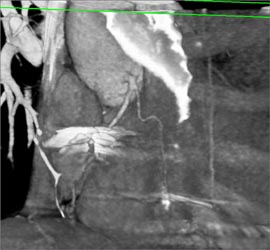

Thickened and Calcified Aortic Valve